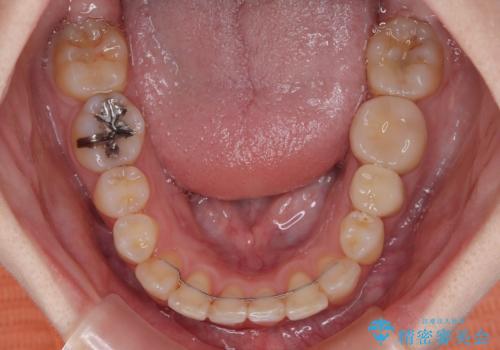

事前にむし歯の疑いがある歯があり、処置を行いましたが、矯正治療中に失活してしまい、ワイヤー装置除去後に、根管治療とセラミッククラウンによる補綴治療を行いました。

矯正治療は2年半ほで無事におけることができました。